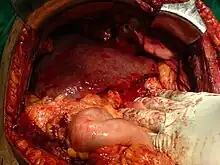

Liver allografts for transplant usually come from donors who have died from fatal brain injury. Living donor liver transplantation is a technique in which a portion of a living person's liver is removed (hepatectomy) and used to replace the entire liver of the recipient. This was first performed in 1989 for pediatric liver transplantation. Only 20 percent of an adult's liver (Couinaud segments 2 and 3) is needed to serve as a liver allograft for an infant or small child.

More recently, adult-to-adult liver transplantation has been done using the donor's right hepatic lobe, which amounts to 60 percent of the liver. Due to the ability of the liver to regenerate, both the donor and recipient end up with normal liver function if all goes well. This procedure is more controversial, as it entails performing a much larger operation on the donor, and indeed there were at least two donor deaths out of the first several hundred cases. A 2006 publication addressed the problem of donor mortality and found at least fourteen cases.[74] The risk of postoperative complications (and death) is far greater in right-sided operations than that in left-sided operations.

With the recent advances of noninvasive imaging, living liver donors usually have to undergo imaging examinations for liver anatomy to decide if the anatomy is feasible for donation. The evaluation is usually performed by multidetector row computed tomography (MDCT) and magnetic resonance imaging (MRI). MDCT is good in vascular anatomy and volumetry. MRI is used for biliary tree anatomy. Donors with very unusual vascular anatomy, which makes them unsuitable for donation, could be screened out to avoid unnecessary operations.

MDCT image. Arterial anatomy contraindicated for liver donation

MDCT image. Arterial anatomy contraindicated for liver donation MDCT image. Portal venous anatomy contraindicated for liver donation

MDCT image. Portal venous anatomy contraindicated for liver donation MDCT image. 3D image created by MDCT can clearly visualize the liver, measure the liver volume, and plan the dissection plane to facilitate the liver transplantation procedure.

MDCT image. 3D image created by MDCT can clearly visualize the liver, measure the liver volume, and plan the dissection plane to facilitate the liver transplantation procedure. Phase contrast CT image. Contrast is perfusing the right liver but not the left due to a left portal vein thrombus.

Phase contrast CT image. Contrast is perfusing the right liver but not the left due to a left portal vein thrombus.